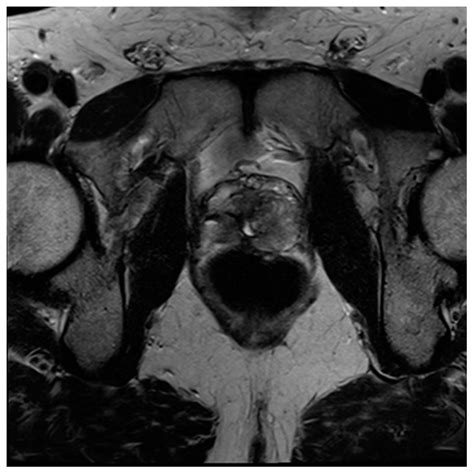

• Size and Shape of the Prostate: The MRI can show the overall size and shape of the prostate, which can indicate conditions like BPH.

• Tumors or Lesions: The presence of tumors or lesions within the prostate can be detected and characterized based on their size, shape, and location.

• Extracapsular Extension: MRI can determine if the cancer has spread beyond the prostate capsule, which is crucial for staging and treatment planning.

• Lymph Node Involvement: The MRI can also assess nearby lymph nodes for signs of cancer spread.